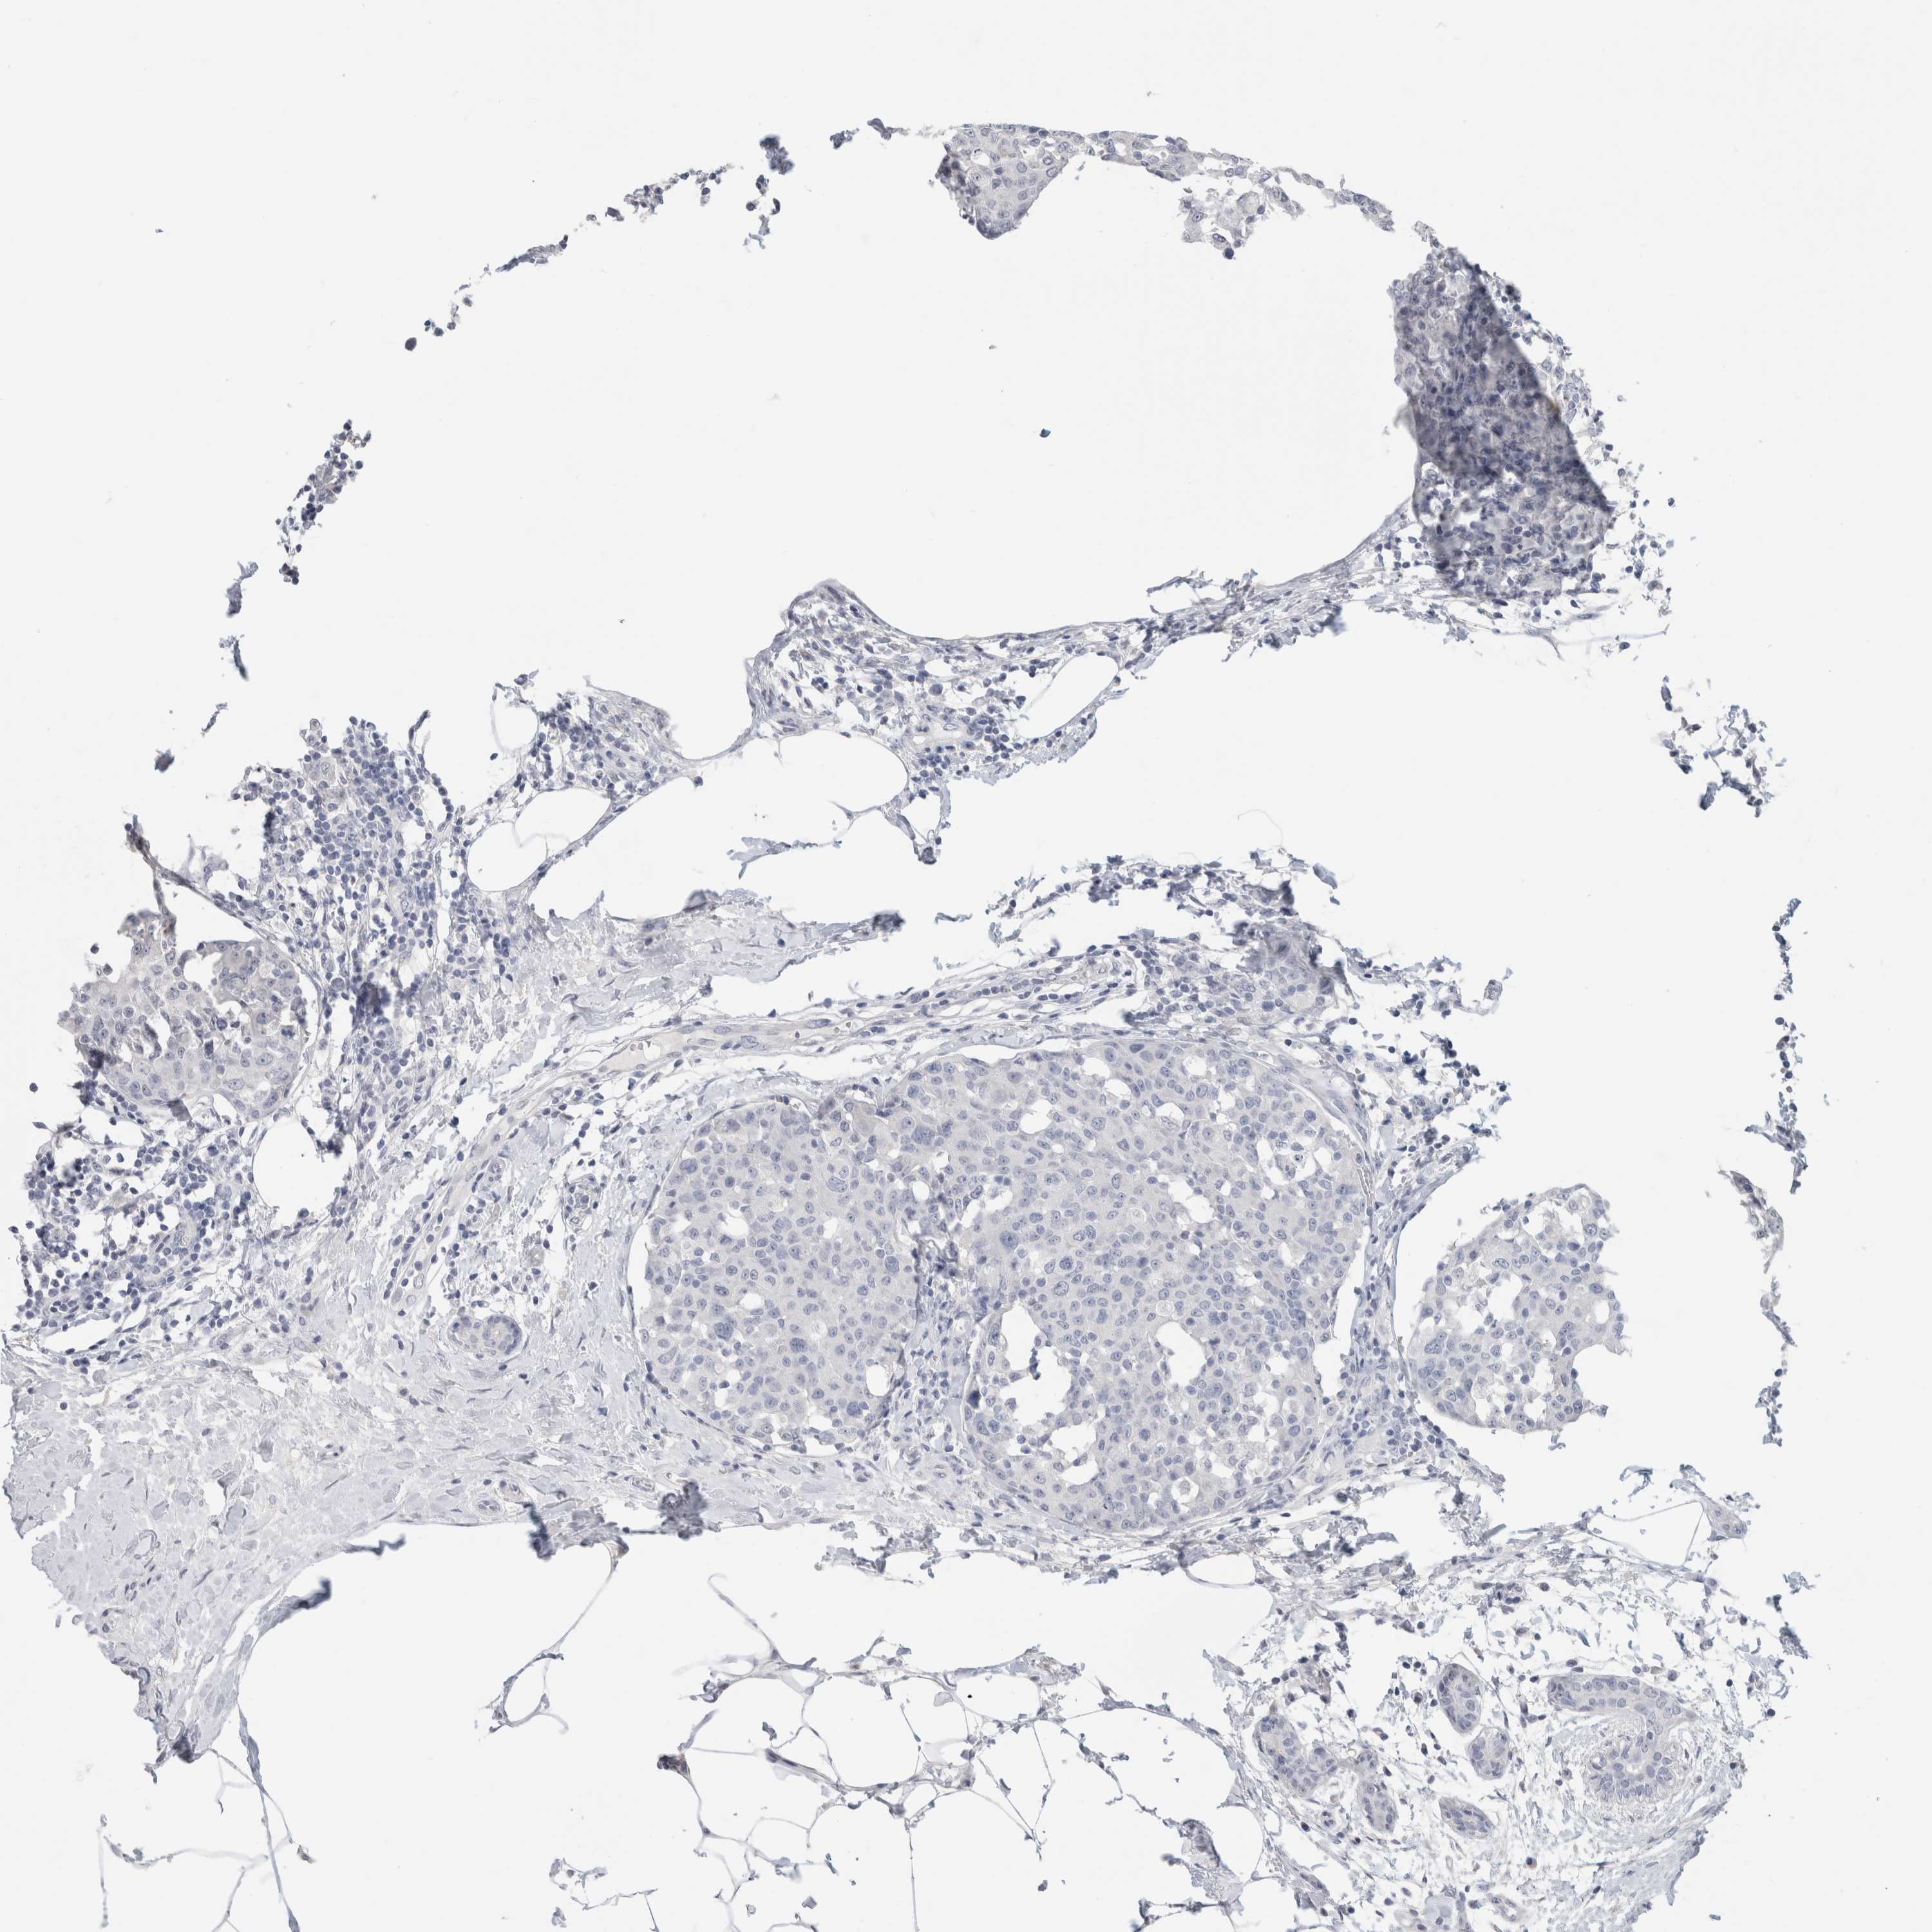

CANCER BREAST CANCER Show tissue menu

BRCA TCGA BRCA VALIDATION PROTEIN EXPRESSION